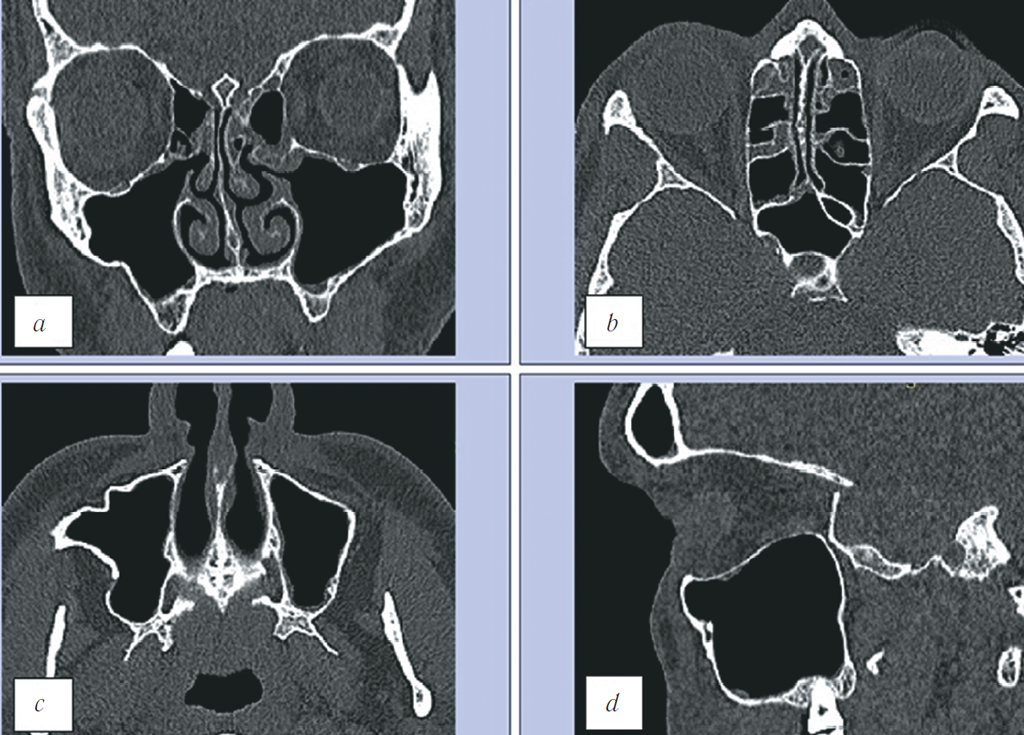

У пациента было диагностировано повреждение лицевого скелета справа: перелом латеральной и нижней стенок правой орбиты, перелом латеральной и передней стенки правого верхнечелюстного синуса и двойной перелом правой скуловой дуги. Перелом нижней стенки орбиты классифицировался по типу «взрывного» с локализацией в центрально-латеральном отделе, пролабирования мягкотканных структур орбиты в верхнечелюстной синус не выявили (рис. 4). По данным компьютерной томографии не представлялось возможным оценить изменение объёма правой орбиты для сравнения с контралатеральной стороной. С этой целью была применена разработанная нами методика обработки МСКТ-изображений, расчёта объёмов обеих орбит и представления их в миллиметрах для детальной оценки посттравматических изменений структур средней зоны лица.

Рис. 4. МСКТ, средняя зона лица, костный режим. Коронарная (a), аксиальная (b, c) и сагиттальная (d) реконструкции. Травматические повреждения лицевого скелета справа: перелом латеральной и нижней стенок правой орбиты, перелом латеральной и передней стенок правого верхнечелюстного синуса в области скуловерхнечелюстного шва и двойной перелом правой скуловой дуги

Fig. 4. MSCT, midface, bone window. Coronal (a), axial (b, c), and sagittal (d) reconstructions. MSCT revealed fracture of right orbital floor and of lateral wall, of anterior and lateral maxillary sinus walls, and fractures of zygomatic arch. There was no herniation of orbital content into the maxillary sinus

В рамках динамического обследования пациенту была проведена МСКТ через 2 года после получения травмы. На изображениях отмечается восстановление костных стенок правой орбиты, а также восстановление стенок правого верхнечелюстного синуса и скуловой дуги, при этом визуализируется деформация латеральной стенки синуса (рис. 6). Пролабирования мягких тканей правой орбиты в верхнечелюстной синус не определяли.

Рис. 6. МСКТ, средняя зона лица, костный режим. Коронарная (a), аксиальная (b, c) и сагиттальная (d) реконструкции. На полученных изображениях отмечается восстановление костных стенок правой орбиты, а также восстановление стенок правого верхнечелюстного синуса и скуловой дуги, при этом визуализируется деформация латеральной стенки синуса. Пролабирования мягких тканей правой орбиты в верхнечелюстной синус не определяется

Fig. 6. MSCT, midface, bone window. Coronal (a), axial (b, c), and sagittal (d) reconstructions. On obtained images, there is a bony walls’ repair of the right orbit, as well as of those of right maxillary sinus and of zygomatic arch; at the same time there is a deformation of maxillary sinus lateral wall. There is no herniation of right orbit soft tissues into the maxillary sinus